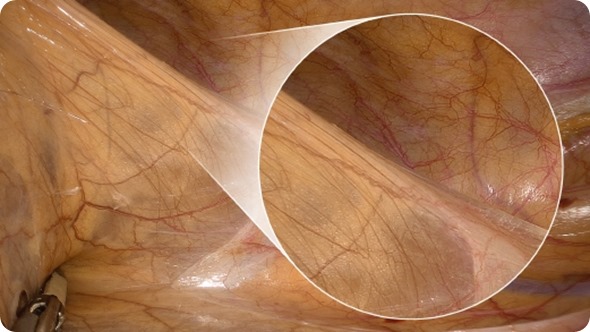

An enlarged color spectrum encompassing around one billion colors is now reality. The system improves the visibility of edges and fine details of delicate tissue, such as blood and lymphatic vessels and nerves. Above all, the richer reproduction of reds assists surgeons in ensuring that incisions are even more accurate.

VISERA 4K UHD: The endoscopy system offers surgeons four times higher resolution to support highly precise surgical procedures

UHD Resolution of an Endoscopy